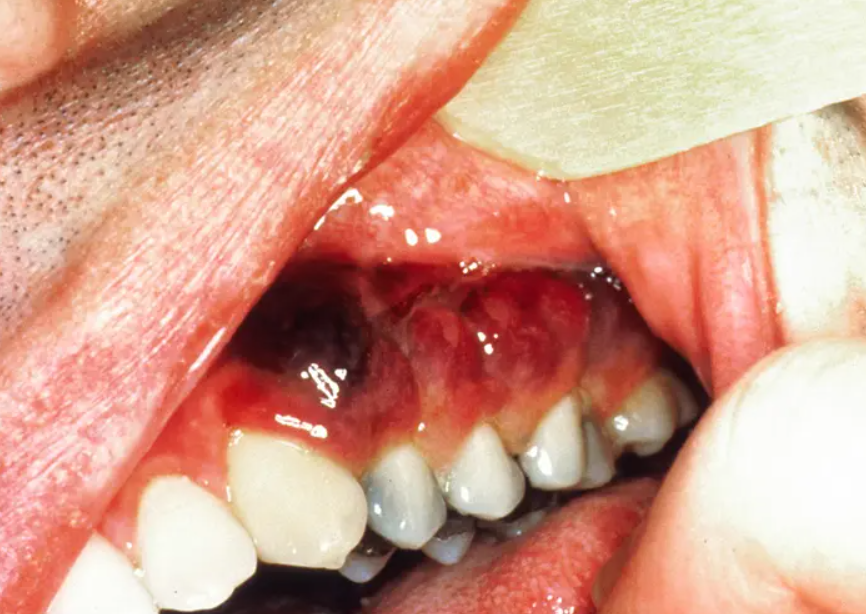

림프관의 벽, 내피세포에서 기인한것으로 생각되는 방추형의 세포들로이루어진 종양 덩어리가,

서서히 자라는데, 이것이 피부나 점막에서 발견됩니다.

HHV human herpes virus 8 에 의해서 발생하는 악성종양으로, AIDS 환자에서 발견되는 경우는,

상당히 진행된 경우에 발생하며, 전신피부, 림프절, 위장관으로 병변이 퍼지면서, 사망률을 높이게됩니다.

초기에는 결막하 출혈과 유사하게 보이게되는데,

실제로는 아래쪽 결막 구석에 발생하는 선홍색의 혈관성 종괴로,

대개는 성장이 느려 작은 병변은 치료가 필요하지 않으나,

크기가 큰 병변은 방사선으로 치료하게됩니다.